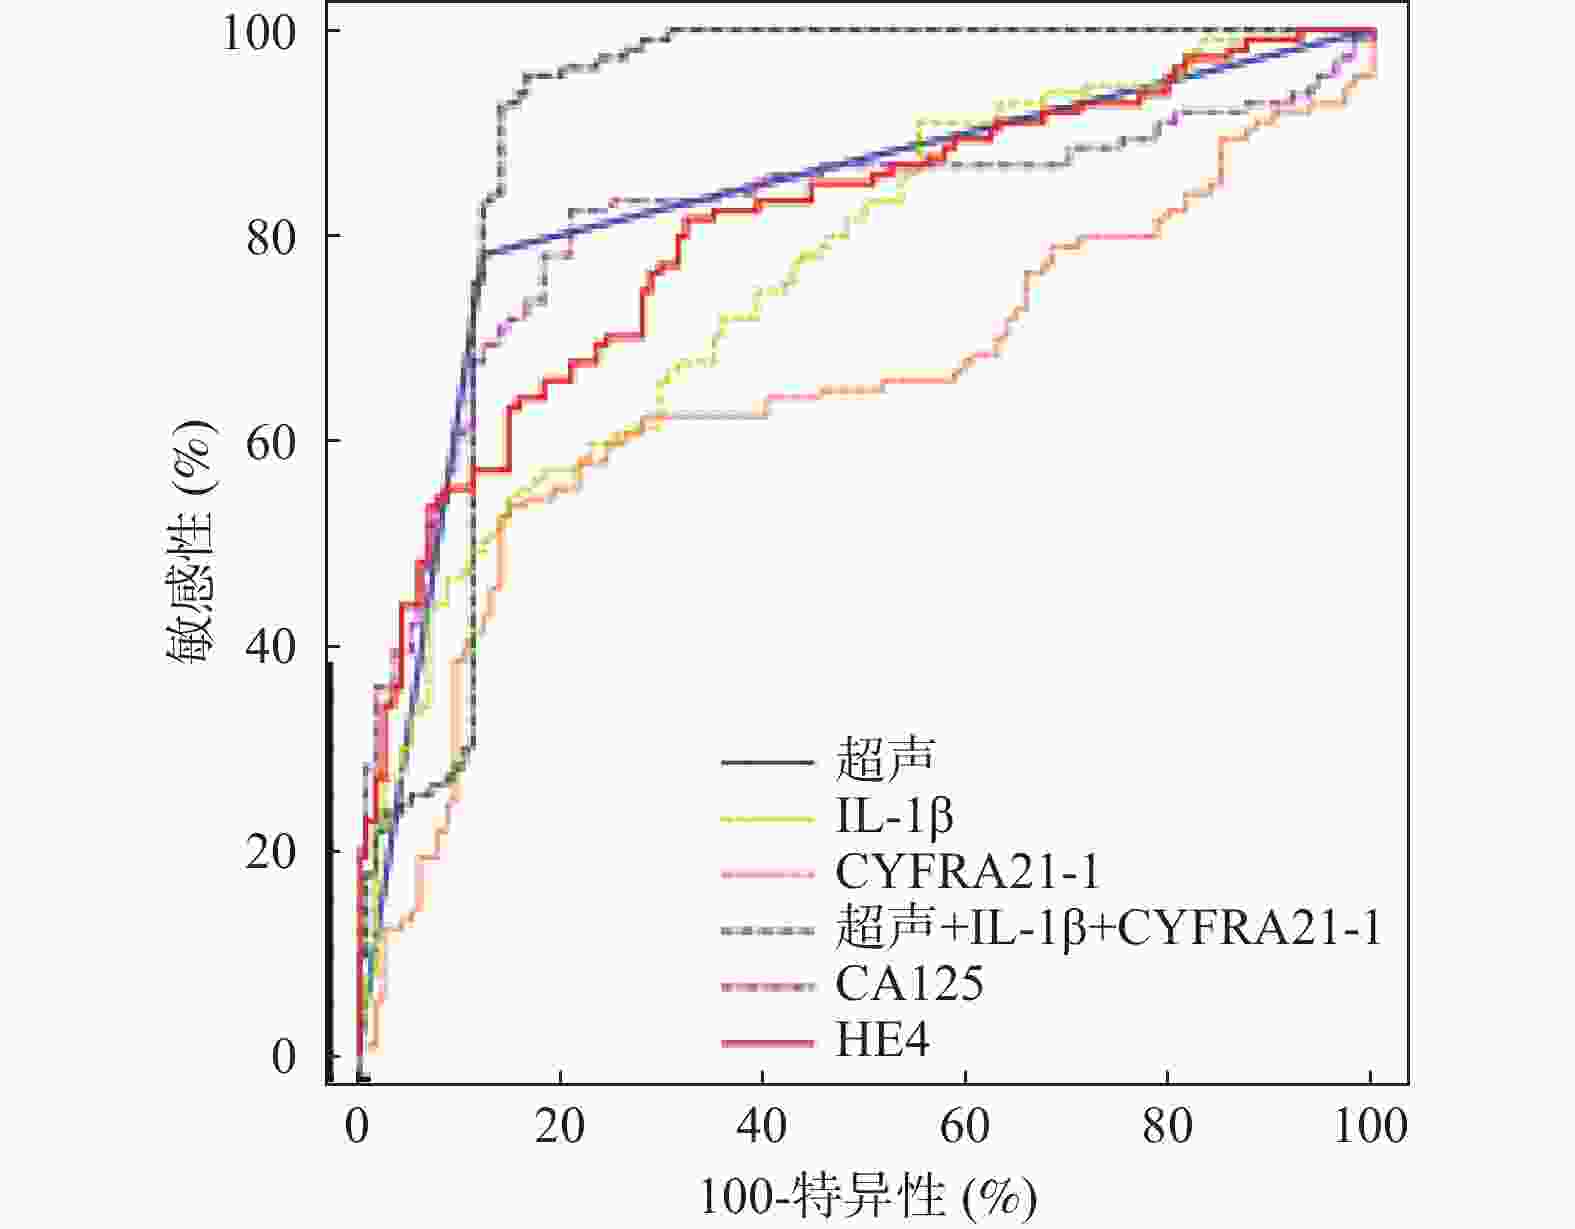

目的 探究超声联合血清白细胞介素-1β(interleukin-1β,IL-1β)、C角蛋白19片段抗原21-1(cytokeratin 19 fragment antigen 21-1,CYFRA21-1)对卵巢癌的诊断价值。 方法 于2020年7月至2023年7月选取沧州中西医结合医院收治的卵巢肿瘤患者250例,经病理检测确诊为卵巢癌的患者114例即为卵巢癌组,从136例良性肿瘤患者中随机选择114例卵巢良性病变患者即为对照组。采用彩色超声诊断仪对所有研究对象进行诊断。采用酶联免疫吸附(enzyme linked immunosorbent assay,ELISA)法检测血清中IL-1β、CYFRA21-1水平。Kappa检验分析诊断方法与手术病理结果的一致性。多因素Logistic回归分析卵巢癌发生影响因素。受试者工作特征(receiver operating characteristic,ROC)曲线分析超声联合血清IL-1β、CYFRA21-1对卵巢癌的诊断价值。 结果 卵巢癌组患者血清中IL-1β、CYFRA21-1水平与对照组相比显著升高(P < 0.05)。与透明细胞癌相比,粘液性腺癌和浆液性腺癌患者血清中IL-1β、CYFRA21-1水平依次显著升高(P < 0.05)。卵巢癌患者血清中IL-1β、CYFRA21-1水平在Ⅰ期<Ⅱ期<Ⅲ期<Ⅳ期(P < 0.05)。血清IL-1β、CYFRA21-1水平升高是卵巢癌发生的危险因素(P < 0.05)。超声联合血清IL-1β、CYFRA21-1对卵巢癌诊断的曲线下面积(area under the curve,AUC)显著高于单一指标诊断的AUC值(Z超声~超声+IL-1β+CYFRA21-1=3.782,P < 0.001;ZIL-1β~超声+IL-1β+CYFRA21-1=4.046,P < 0.001;ZCYFRA21-1~超声+IL-1β+CYFRA21-1=7.279,P < 0.001)。以病理检查结果为依据,联合诊断的一致性(Kappa值=0.789)高于超声(Kappa值=0.658)单独诊断。 结论 超声联合血清IL-1β、CYFRA21-1对卵巢癌的诊断效能较高。 -

Abstract:Objective To explore the diagnostic value of ultrasound combined with serum interleukin-1β (IL-1β) and cytokeratin 19 fragment antigen 21-1 (CYFRA21-1) in ovarian cancer. Methods From July 2020 to July 2023, 250 patients with ovarian tumors admitted to Cangzhou Integrated Chinese and Western Medicine Hospital were enrolled. Among them, 114 patients confirmed as having ovarian cancer by pathological examination comprised the ovarian cancer group. Additionally, 114 patients were randomly selected from the remaining 136 patients with benign tumors to form the control group. All study subjects underwent diagnosis using color ultrasound diagnostic equipment. Serum levels of IL-1β and CYFRA21-1 were detected using the enzyme linked immunosorbent assay (ELISA) method. Kappa test was used to analyze the consistency between diagnostic methods and surgical pathological results. Multivariate logistic regression analysis was performed to identify risk factors for ovarian cancer occurrence. Receiver operating characteristic (ROC) curve analysis was used to evaluate the diagnostic value of ultrasound combined with serum IL-1β and CYFRA21-1 for ovarian cancer. Results Serum levels of IL-1β and CYFRA21-1 in the ovarian cancer group were significantly elevated compared to the control group (P < 0.05). Compared with clear cell carcinoma, serum levels of IL-1β and CYFRA21-1 in patients with mucinous adenocarcinoma and serous adenocarcinoma were significantly elevated (P < 0.05). Serum levels of IL-1β and CYFRA21-1 in ovarian cancer patients showed a progressive increase across stages I<stage II<stage III<stage IV (P < 0.05). Elevated serum levels of IL-1 β and CYFRA21-1 were risk factors for ovarian cancer (P < 0.05). The area under the curve (AUC) for the combined ultrasound with serum IL-1β and CYFRA21-1 in diagnosing ovarian cancer was significantly higher than the AUC values of single-indicator diagnosis (Zultrasound~ultrasound+IL-1β+CYFRA21-1=3.782, P < 0.001; ZIL-1β~ultrasound+IL-1β+CYFRA21-1=4.046, P < 0.001; ZCYFRA21-1~ultrasound+IL-1β+CYFRA21-1=7.279, P < 0.001). Based on pathological examination results, the consistency of combined diagnosis (Kappa value=0.789) was higher than ultrasound alone (Kappa value=0.658). Conclusion The combined diagnostic approach of ultrasound with serum IL-1β and CYFRA21-1 demonstrates high diagnostic efficacy for ovarian cancer. -